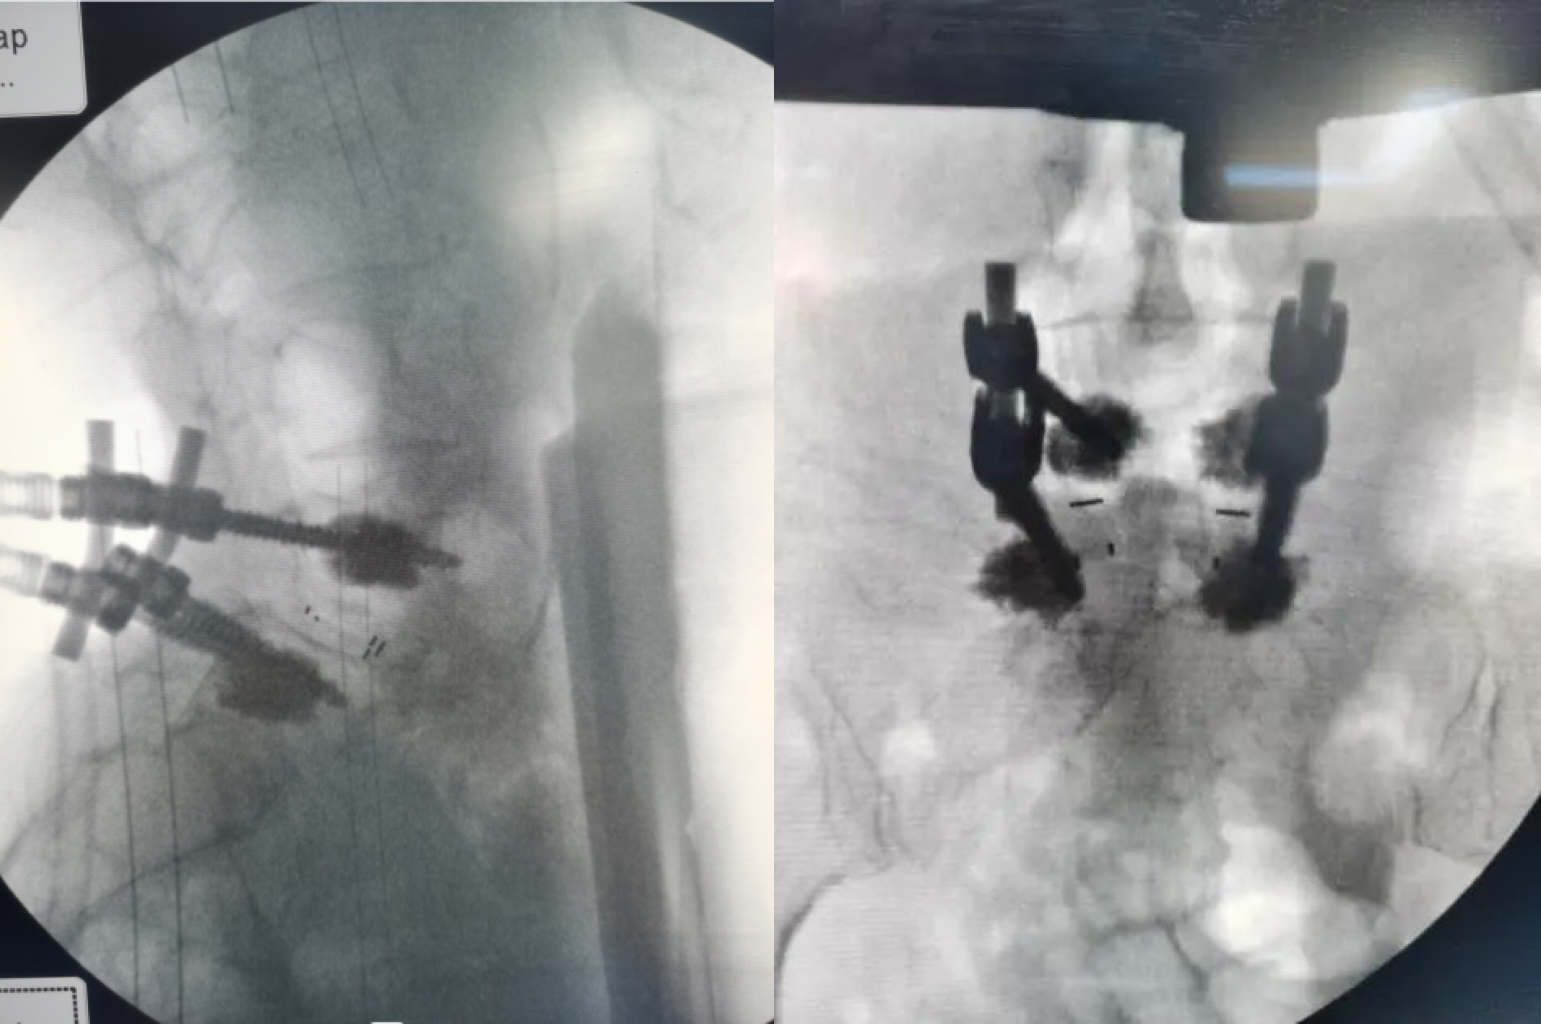

德康LEO骨水泥螺釘系統(tǒng)應用效果展示

1.病例一

2.病例二